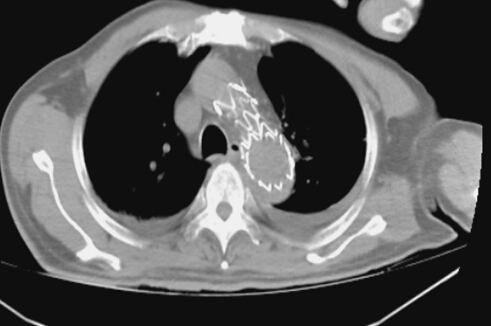

術前見主動脈夾層,胸腔大量積液和血凝塊

2014年3月18日20點55分,呼嘯而至的120救護車在郴州市第一人民醫(yī)院中心醫(yī)院急診室嘎然停下。初步檢診后明確患者既往有高血壓病史8年余,10余天突發(fā)劇烈胸背部疼痛,1小時前因突然暈厥而被120急診送入院。醫(yī)院綠色通道迅速啟動,相關科室10多位已經下班回家的醫(yī)護人員被緊急召回,時間就是生命,一場生死營救迅速展開。老人直接從急診室轉送至ICU病房,予快速補液、抗休克等對癥支持治療,病人生命體征逐漸趨于平穩(wěn),緊急完成主動脈CTA后,診斷患者胸主動脈夾層,胸腔大量積液及血凝塊。 血管外科病區(qū)主任鄭翼德副主任醫(yī)師在仔細查看病人后考慮患者有主動脈夾層破裂可能。 ?

各相關科室醫(yī)護人員迅速準備到位,成立搶救小組,各司其職。鄭翼德主任在大血管介入治療方面有著豐富的經驗,搶救小組經過仔細討論研究,決定對患者實施胸主動脈帶膜支架腔內隔絕術。緊急氣管插管、麻醉、股動脈切開、主動脈造影,一切都有條不紊地進行。透視監(jiān)視下,導絲導管從股動脈進入,向上“游”走到升動脈弓處,造影明確夾層破口位置及撕裂情況,選取適當支架系統(tǒng),在支架穩(wěn)穩(wěn)妥妥地放入預定主動脈內后,再次造影顯示破口完全封堵,未見經內漏繼續(xù)出血,手術取得圓滿成功。大家雖然苦了、累了,汗流浹背,卻個個露出了開心的笑容。